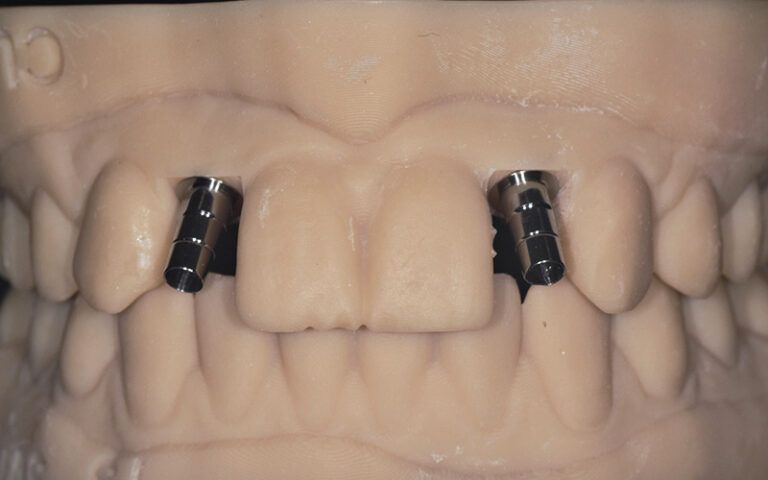

Details of the laboratory work with titanium bases on a digital model printed in 3D Details of the laboratory work with titanium bases on a digital model printed in 3D Details of the laboratory work with titanium bases on a digital model printed in 3D